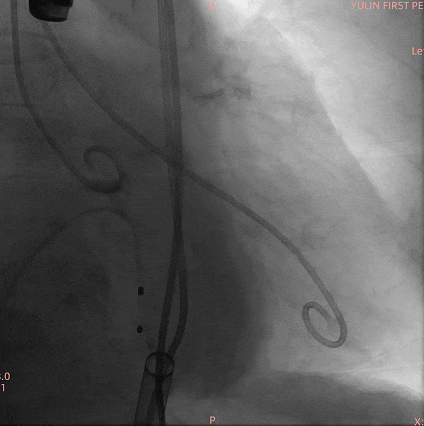

手术过程

通过术前精准评估,患者在全麻下行TAVR手术,DSA和食道超声双重引导,通过穿刺心尖建立工作路径,沿加硬导丝送入19mm*40mm球囊预扩张主动脉瓣,球囊无腰有漏,利用短鞘送入25#RENATUS瓣膜至左室,猪尾巴导管再次造影确认位置。将25#RENATUS瓣膜顺利跨瓣,精准定位,5ATM精确释放,退出输送系统再次行主动脉根部造影,示瓣膜膨胀充分,无瓣口反流,无瓣周漏,冠脉血流正常,术后即刻平均跨瓣压差降至3.62mmHg,超声示术后峰值流速降至0.95m/s。瓣膜释放位置理想、形态及功能良好,瓣叶启闭良好,无外周血管损伤。

主动脉根部造影

19mm球囊预扩无腰有漏

25#Renatus瓣膜造影定位

快速起搏下5atm精准球扩释放25#Renatus瓣膜

释放后造影示瓣膜位置理想,形态良好